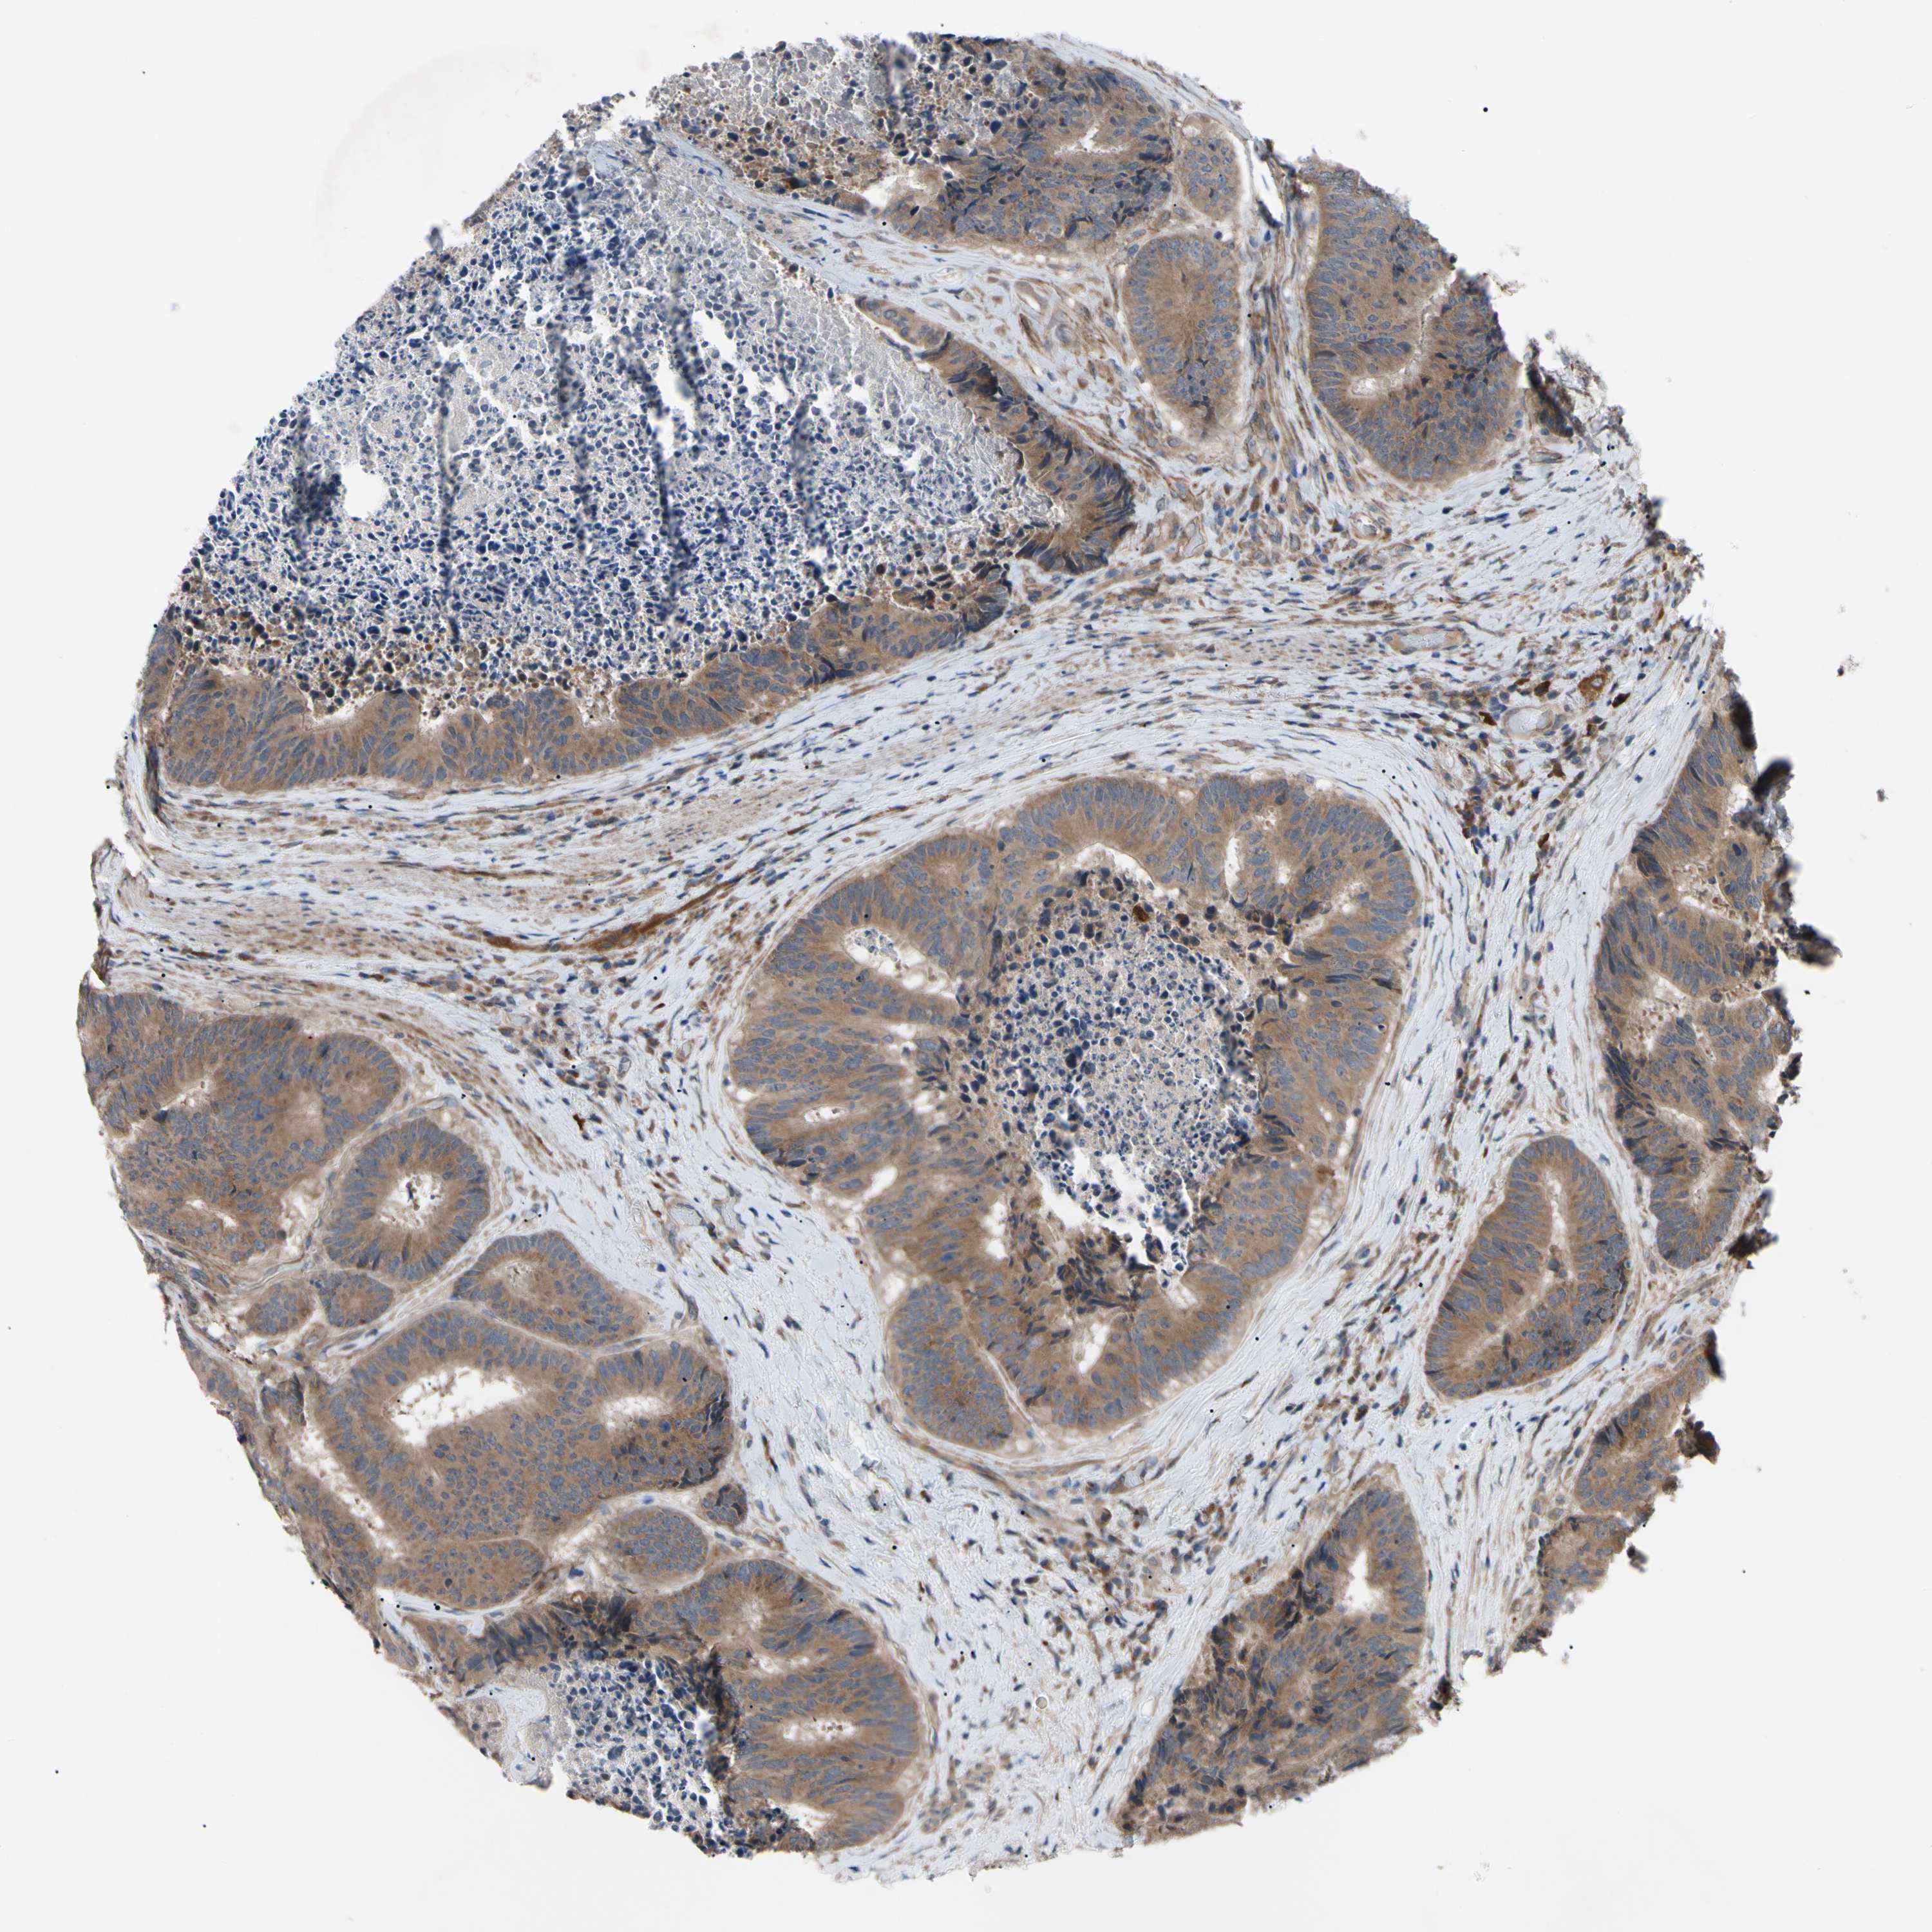

Colorectal cancer

Human cancer

Colon adenocarcinoma

Rectum adenocarcinoma